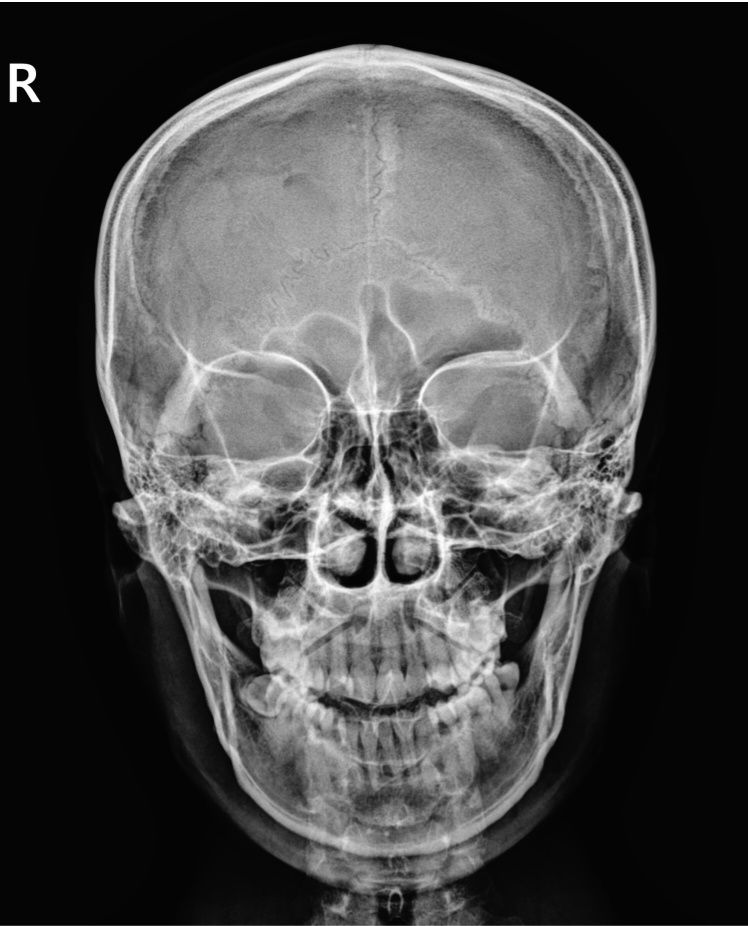

2번째 사진에 접형골이 밑으로 내려와서 상악동이 좁아졌잖아요

이렇게 접형골 위치가 바뀌는게 가능한가요?

너무걱정되요

• 2번 째 사진

접형골은 두개골 깊숙한 중심부에 있어 위치가 크게 바뀌는 것은 외상이나 선천적 구조외엔 매우 드뭅니다.

엑스레이는 입체적 구조를 평면으로 찍기 때문에 왜곡이나 겹침 현상으로 위ㅣ가 다르게 보일 수 있어요 정확한 진단은 CT나 전문의 판독이 필요하므로 이비인 후과나 신경외과 상담을 추천드립니다!